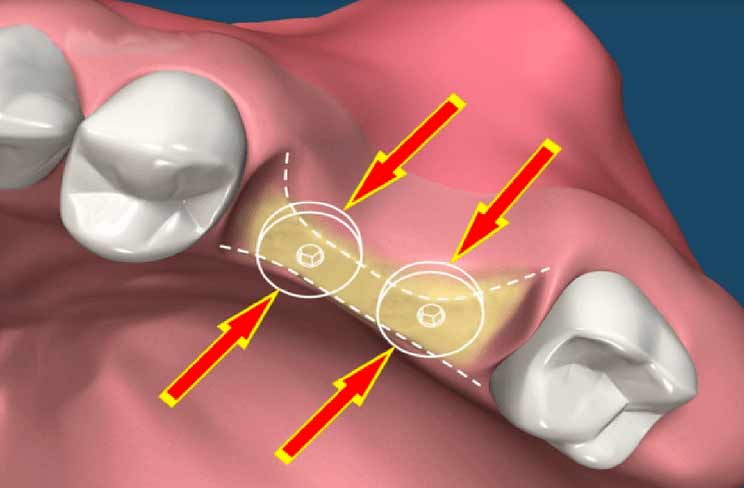

تحلیل عرضی استخوان

پیوند استخوان در فک دارای شیوه های مختلفی است. برای افزایش طول استخوان برای فک بالا، عمدتاً از روش سینوس لیفت استفاده میشود. در این روش، پس از تحلیل یا کاهش ارتفاع استخوان، سینوسها برای فراهم کردن فضای لازم به سمت پایین میآیند. سپس با استفاده از تکنیک سینوس لیفت، سینوسها به بالا برده شده و با پودر استخوان، فضای خالی بین آنها پر میشود. برای افزایش عرض استخوان نیز میتوان از روش ریج اسپلیت بهره گرفت. این روش، اگرچه در همه جا قابل اجرا نیست، اما میتواند به بهبود عملکرد ایمپلنت کمک کند. لازم به ذکر است که هر دو روش نیازمند دقت و مهارت بالای جراحی است و باید توسط یک جراح متخصص اجرا شود.

پیوند استخوان فک برای تحلیل عرضی استخوان